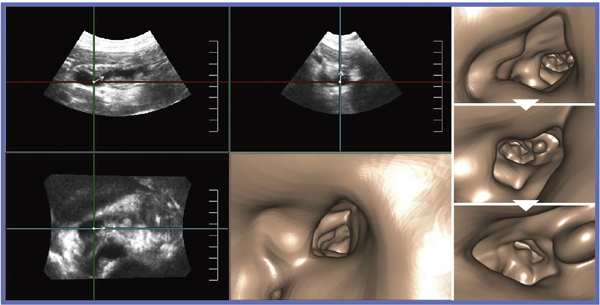

Cavity(USCP)では,主膵管拡張の状態を表現することができる。しかしながら,当然,内腔面の変化はわからない(図7)。膵頭部から膵尾部方向にFly Thruすると,内腔に突出した複数の乳頭状腫瘤を認識できた(図8)。

図8 症例3:IPMNのFly Thru画像(膵頭部から膵尾部方向へ)

Fly Thruの課題は,表示された内腔面が本当に実際の内腔面を表しているかである。Fly Thruの内腔面の表示は,閾値の設定によって変更できる。現在は閾値は自動設定されており,本当にそれが最適かどうか検者の眼で判断できないのが実情である。また,現在の解像度では,腫瘍や胆石などを判別することが難しい。Fly Thruによって診断に新たな情報を提供するためには,さらなる解像度の向上が望まれる。また,手技などに関する要望として,動画の保存時間(飛行時間)の延長(現在は20秒),表示のバリエーションを増やすことなどを挙げたい。3D画像には,“使いやすい”,“わかりやすい”,“診断しやすい”だけではなく,2Dでは得られない“診断に必要な情報”が求められる。